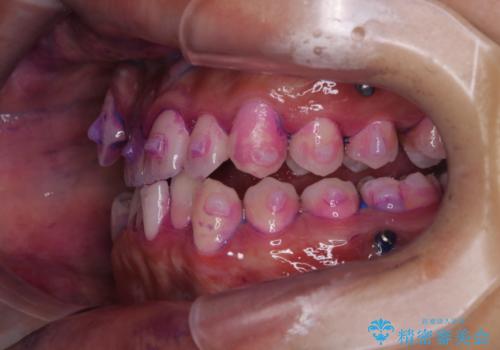

- マウスピース矯正中に、口臭が気になりクリーニングを行いたいとのことでした。染め出しをしての歯ブラシ指導とPMTC60分コースを行いました。

染め出し液を使ってプラークを染め出すことにより、普段の歯みがきで磨き残している場所を目で確かめることができます。